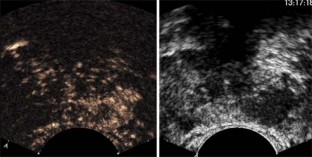

New ultrasound technologies, including color- and power Doppler ultrasound, contrast enhanced US and real-time sonoelastography have shown to improve prostate cancer diagnosis.

Contrast-enhanced ultrasound has shown a sensitivity of 100% (95% CI, 95%), a negative predictive value (NPV) of 99.8% and a positive predictive value (PPV) of 88.8% for prostate cancer detection. Real-time sonoelastography has shown a sensitivity of 86%, a specificity of 81% and NPV of 91% for prostate cancer diagnosis.

Most studies show that these new ultrasound modalities demonstrate a 1.5 to 2.5 times higher detection of prostate cancer per biopsy specimen compared with systematic biopsy. Multicenter studies results are at present lacking but are, however ongoing.

In patients with suspected prostate cancer (elevated PSA, suspicious DRE) these new ultrasound techniques should be used. These techniques can detect prostate cancer and allow a targeted biopsy approach.